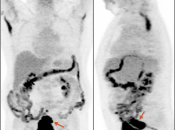

- Normal physiologic bowel uptake (discussed here) can be very focal and isolated to only one part of the colon, most commonly the cecum and rectum. Always look for associated bowel wall thickening on the CT images.

- Hemorrhoids are often intensely avid in the ano-rectal region (and are usually not visible on the CT images). Be certain that uptake does not lie more superiorly in the rectum. Additionally, carefully assess for an accompanying soft tissue density to exclude an anal cancer.

- Beware the small rectal cancer! As the ano-rectal region frequently demonstrates intense physiologic uptake, it is very easy to overlook a rectal malignancy, especially if it is an incidental finding. To avoid this error, always evaluate the rectum carefully on the sagittal whole body images. It is shocking to see how readily apparent a rectal cancer can be on these images, yet so easily overlooked in the axial plane.